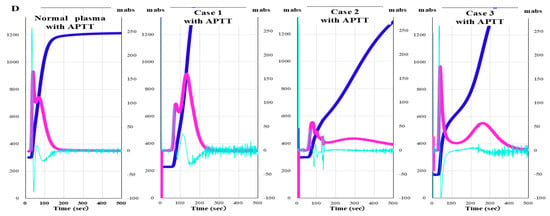

CWA-APTT was measured using patient PPP and HemosIL APTT-SP on an ACL-TOP system based on previously reported methods [29]. The CWA-small amount of tissue factor activation assay (sTF/FIXa) was performed using patient PRP and 2000-fold diluted HemosIL RecombiPlasTin 2G with saline solution including CaCl2 on an ACL-TOP® system [30]. The CWA-sTT of patient PPP was measured using an ACL-TOP® system with 0.2 IU of thrombin, which was diluted with 0.9% saline solution including CaCl2 [26,29]. CWA-sTT was measured with or without 16-fold diluted APTT-SP with 0.9% saline solution. CWA-sTT reflects thrombin burst caused by activated platelets and activated FVIII (FVIIIa), and when APTT reagent is added, it is more strongly affected by FVIIIa. In hemophilia A (HA), since the residual FVIII is extremely low, CWA-sTT is only minimally enhanced; in AiFVIIID, in comparison, it shows mild enhancement (Figure 1).

Clot waveform analysis of clotting time determined using a small amount of thrombin. (A,D) healthy volunteer (HV); (B,E) hemophilia A (HA); (C,F) autoimmune factor VIII deficiency (AiFVIIID); (A–C) without APTT reagent; (D–F) with APTT reagent; APTT, activated partial thromboplastin time; navy line, fibrin formation curve; pink line, first derivative curve (velocity); light blue, second derivative curve (acceleration). In HV, the thrombin burst is enhanced by the addition of APTT reagent, whereas in HA, it is not enhanced, and AiFVIIID is slightly enhanced.

In the CWA-sTT, a small amount of FVIIIa is generated, which counteracts the effect of emicizumab, and since there is no incubation with the APTT reagent, it is considered not to be affected by emicizumab. In the CWA, three types of curves are shown [26,27]. The first represents the change in absorbance observed during the TT measurement, corresponding to the fibrin formation curve (FFC). The second is the first derivative of the absorbance peak (first DP), corresponding to the coagulation velocity. The third is the second derivative of the absorbance peak (second DP), corresponding to the coagulation acceleration.

Anti-FVIII antibody activity: Measuring FVIII activity using CWA-sTT enables sensitive detection of residual FVIII activity in patients with AiFVIIID. The measured residual FVIII activity was converted into the amount of FVIII antibody added to normal plasma. Because CWA-sTT shows a similar pattern in normal plasma regardless of the presence of emicizumab, it can be used to measure FVIII activity in the presence of emicizumab. When anti-FVIII antibodies were added, the peak height of the second derivative curve in the CWA-sTT during FVIII activity measurement correlated with the anti-FVIII antibodies in a dose-dependent manner. Therefore, in the FVIII activity measurement system using CWA-sTT, anti-FVIII antibody activity could be evaluated in the range of 0.02 μg/mL to 10 μg/mL regardless of the presence of emicizumab (Figure 2).

Figure 2.

CWA-sTT for various anti-FVIII antibody concentrations (A) and Standard curve for anti-FVIII antibody concentration using CWA-sTT. (A): Upper section, with emicizumab; lower section, without emicizumab; CWA-sTT, clot waveform analysis–clotting time using a small amount of thrombin; FVIII, clotting factor VIII; Ab, antibody; EMI, emicizumab; DPH, derivative peak height; light blue, second derivative curve (acceleration); Regardless of the presence of emicizumab, CWA-sTT shows a pattern dependent on anti-FVIII antibody levels; CWA-sTT can be used to measure anti-FVIII antibody titers in the presence of emicizumab. (B): Standard curve for the anti-FVIII antibody activity. FVIII activity in the presence of emicizumab was measured using CWA-sTT as previously reported [26]. The second derivative peak height of CWA-sTT in normal plasma diluted tenfold with FVIII-deficient plasma shows linearity across FVIII levels from 0.1% to 100%.